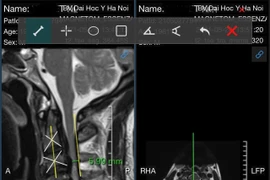

(khoahocdoisong.vn) - Vôi cột sống là để chỉ tình trạng thoái hóa của các dây chằng liên kết các thân đốt sống, các đĩa đệm nằm giữa các thân đốt sống. Cắt bảng sống là lấy đi các thành phần chèn ép để giải áp cho tủy sống.